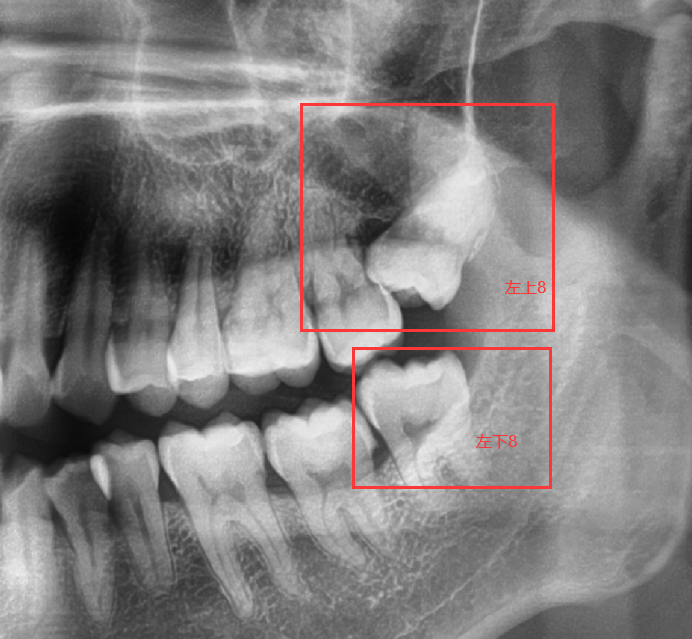

首先,如图,在某次洗牙赠送的口腔全景片中,发现了4颗智齿,相对比别人的智齿,我有2颗智齿位置还不错,另外2颗,就有点问题,今天着重说一下左侧2颗。如图:左上8和左下8。

1、这颗阻生齿抵着左上七这颗牙齿了,硬拔会导致左上七这颗正常牙齿松动;

2、这颗阻生齿的牙根太靠近上颌窦,严重会导致牙根掉进上颌窦内,导致嘴巴和鼻子相通,喝水会从鼻子出来,并且如果真的掉进上颌窦,还得全麻手术取出牙根,并进行消毒。